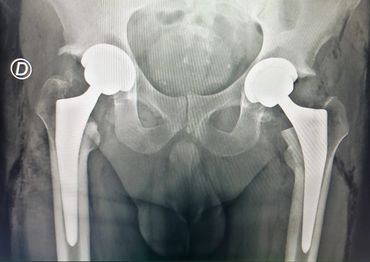

Artroplastía total de cadera bilateral en un tiempo quirúrgico